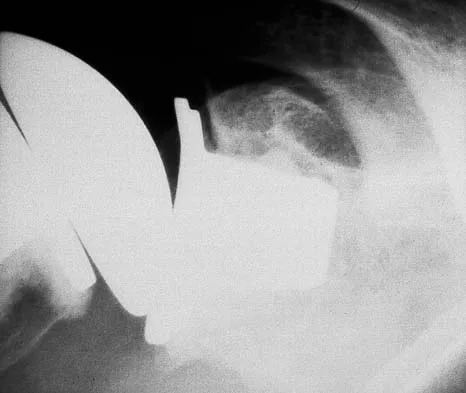

Question 57

A 60-year-old woman has activity-related hip pain after undergoing arthroplasty 5 years ago. She has severe Parkinsonism and denies fevers or chills. Radiographs are shown in Figures 45a and 45b. What is the most likely cause of her pain?

Explanation